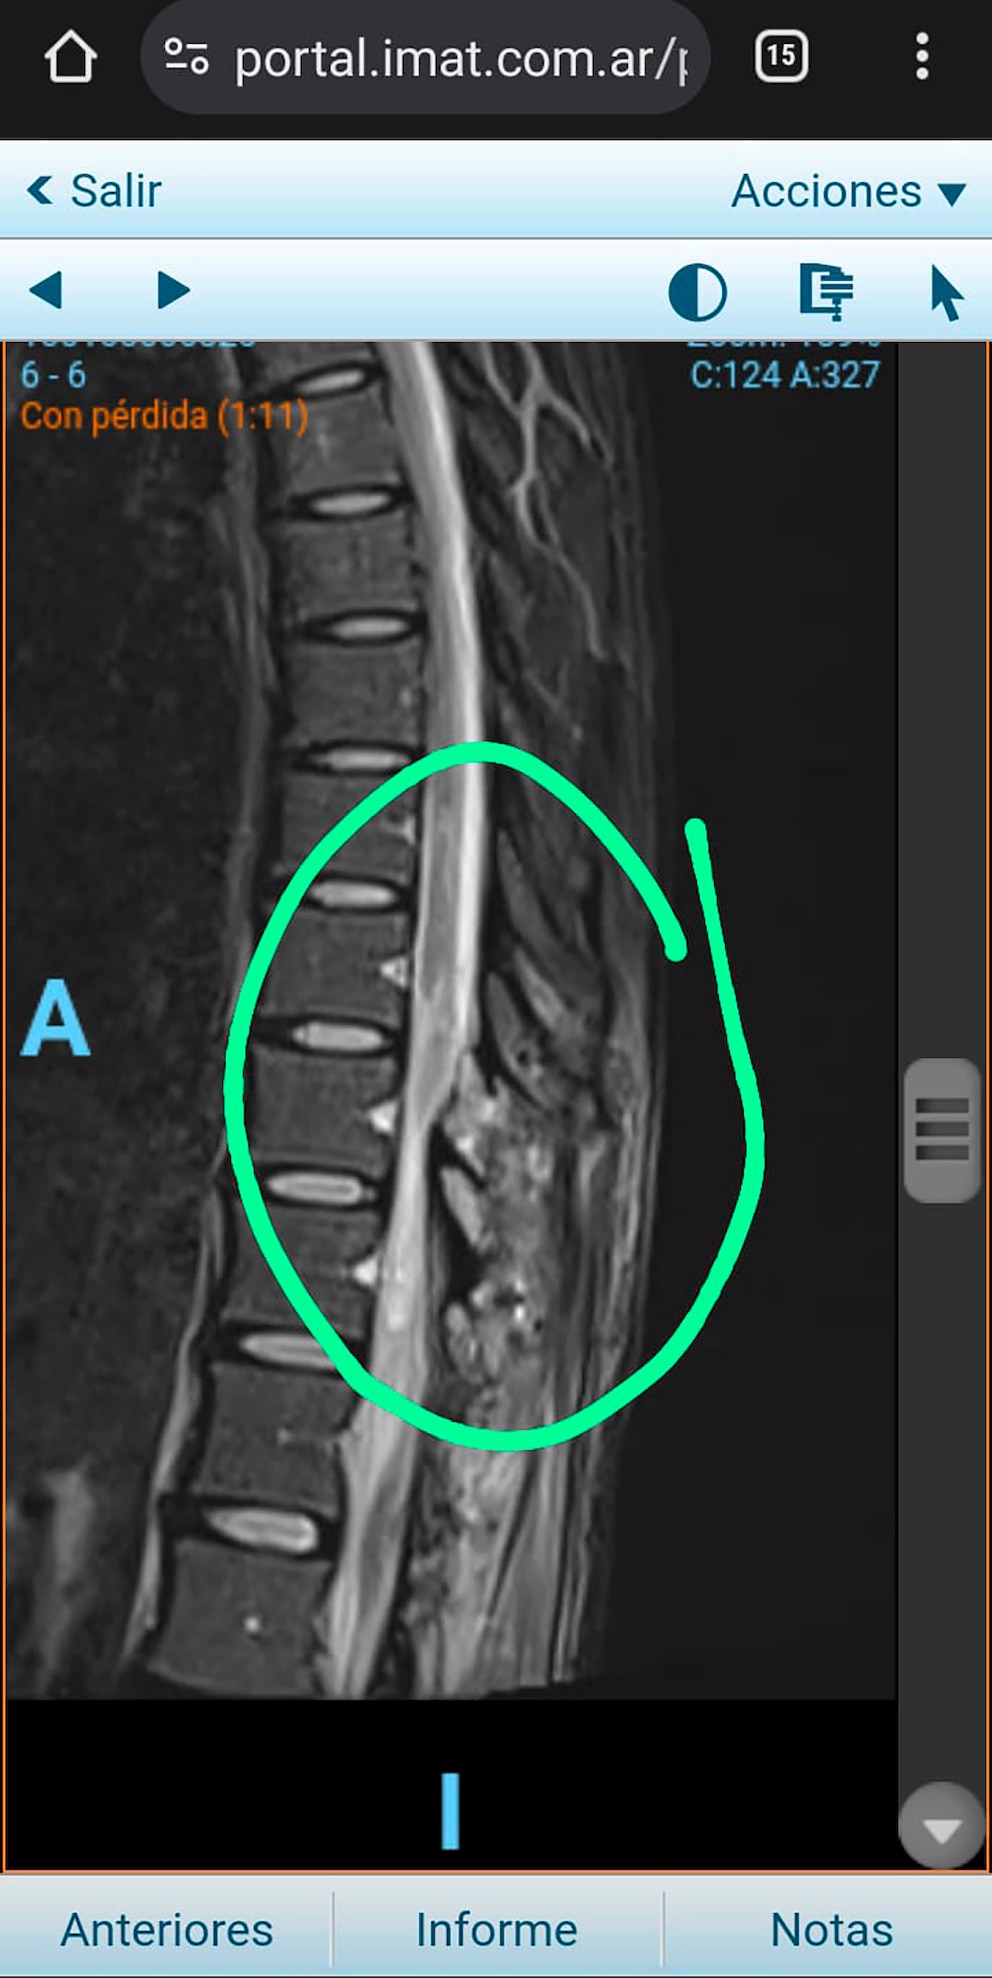

Durante más de 45 días, Antonella permaneció sin un diagnóstico certero. Recién el 2 de marzo, tras reiterados pedidos de su familia, se le practicó una resonancia magnética que reveló una compresión medular provocada por una apófisis espinal. Esa situación obligó a una nueva cirugía de urgencia para descomprimir el canal medular, aunque el daño neurológico ya era severo.